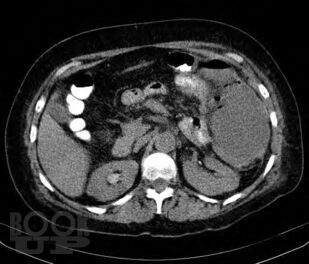

Содержит современные сведения об этиологии, клинической картине, современных аспектах диагностики и лечения несформированных дуоденальных и тонкокишечных свищей.